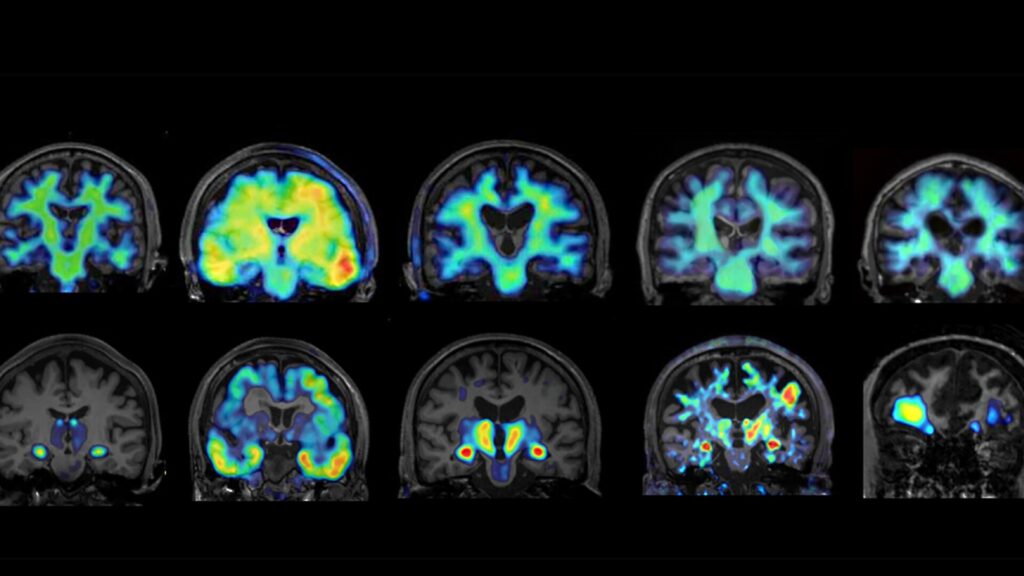

さらに、2023年8月に政府が提唱した「認知症・脳神経疾患研究開発イニシアティブ」を受け、ムーンショット目標7の枠組みのもと、認知症克服を目的とした新たな研究が加速しています。2024年11月からは、「脳内セノインフラメーション」を含む3件の新規プロジェクトが本格的に始動しました。